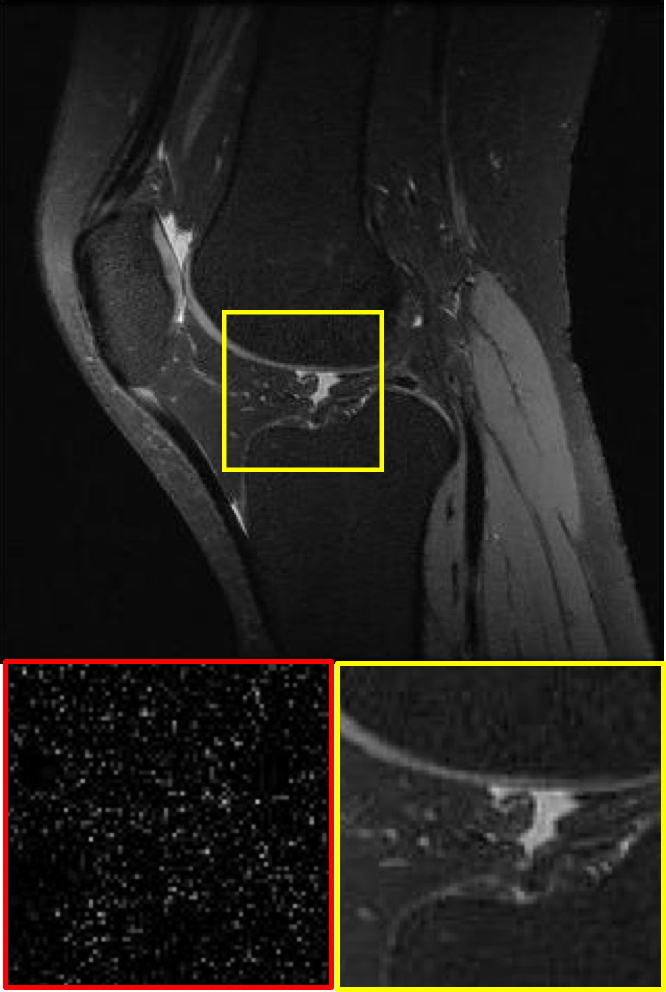

CS MR measurement matrix

LDAMP SURE was applied to CS-MRI reconstruction problem to demonstrate its generality and to show its performance on images that contain structures different from natural image dataset. We compared LDAMP SURE with state-of-the-art BM3D-AMP-MRI algorithm [16] for CS-MR image reconstruction along with TVAL3, BM3D-AMP, and dictionary learning method or DL-MRI [34]. Average image recovery PSNRs and run times are tabulated in Table 3. Figure 5 shows that our proposed method yielded state-of-the-art performance, close to the ground truth. The results reveal that proposed LDAMP SURE-T outperforms existing algorithms in all sampling ratios.

Ground truth

TVAL3

BM3D-AMP

DL-MRI

BM3D-AMP-MRI

LDAMP SURE-T